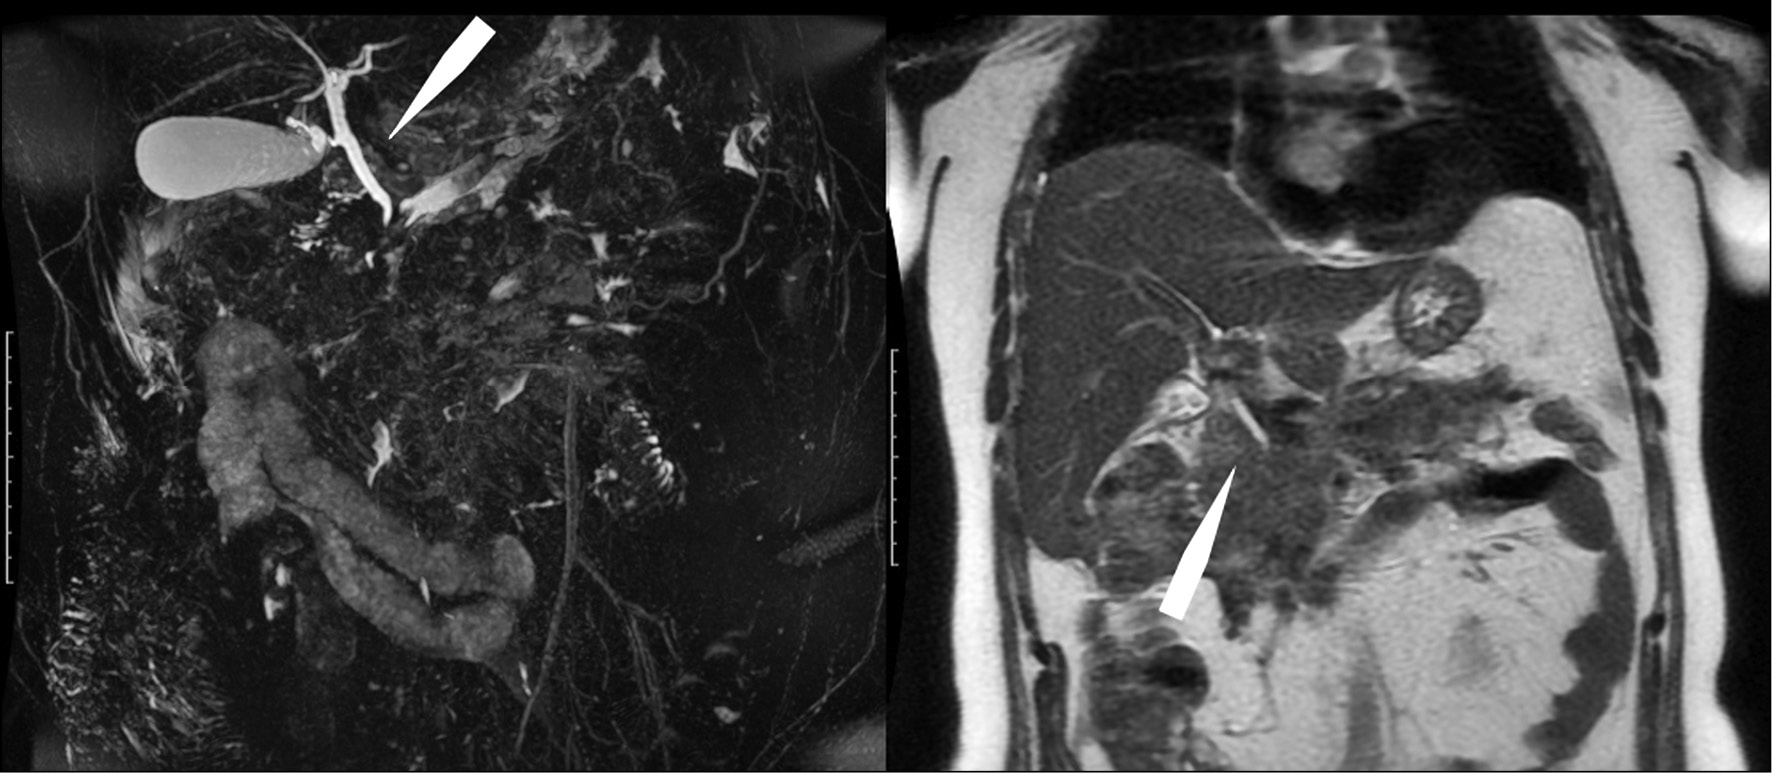

Clinically, the formation of an external pancreatic fistula was noted. On February 28, 2018, the patient underwent MR cholangiography, which revealed that the Wirsung’s duct at the level of the head and body of the pancreas was not visualized; that it had a tortuous course in the tail, with uneven contours and a diameter of 2 mm; and that no fistulous tracts were detected. Intra- and extrahepatic bile ducts were not dilated (Fig. 5).

Fig. 5. Magnetic resonance tomographic cholangiography (left) and T2-VI (coronal plane, right). The distal part of the choledochus is "lost" in the infiltrate, the proximal part of the choledochus and the intrahepatic bile ducts are not dilated (arrows).

In pancreatic necrosis, MRI is the method of choice for assessing the condition of the common bile duct and the Wirsung’s duct, which was very important for our patient who developed an external pancreatic fistula during the treatment of necrotic pancreatitis.